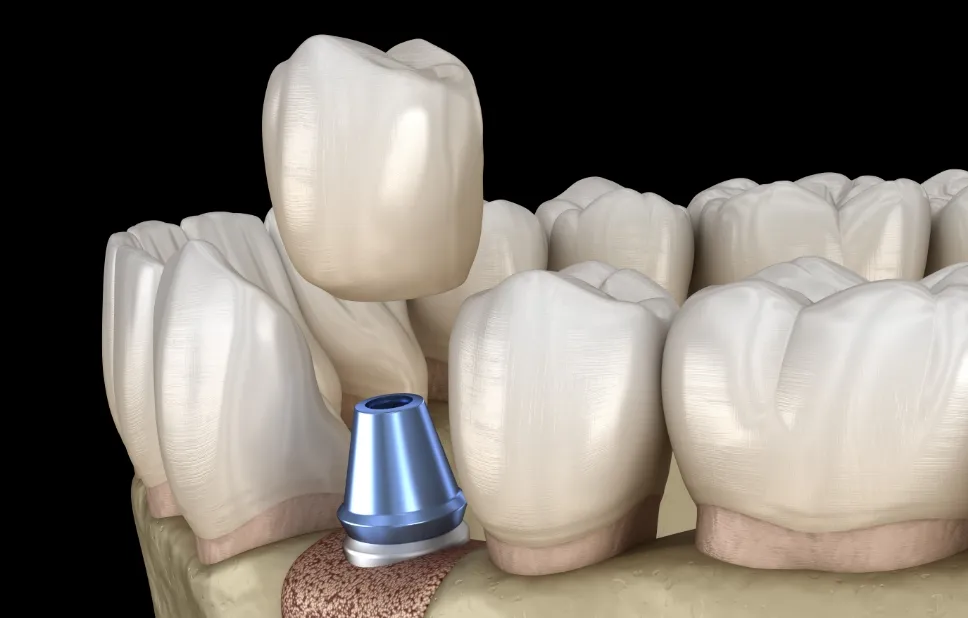

上部構造の作製・装着

インプラントと骨が結合する治癒期間を経て、歯型を取り上部構造を作製します。噛み合わせを整えるとともに見た目が自然になるように仕上げ、装着していただいて完了になります。